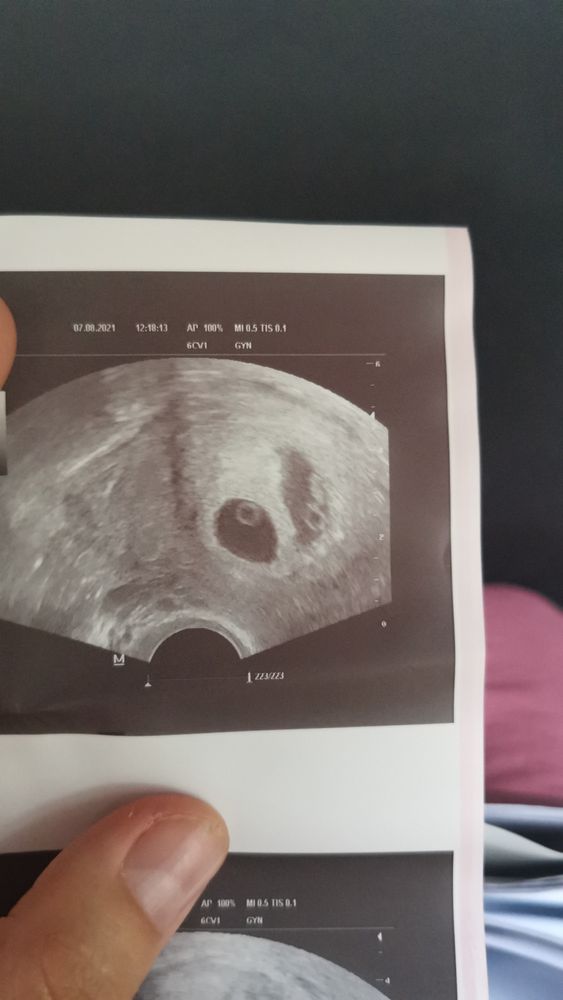

Двойня ЭКО+ЕБ

Мечты сбываются ✨ Продолжение моей истории. ХГЧ на 18 дпп.